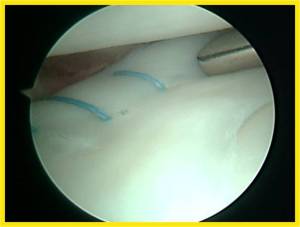

This meniscus tear was repaired using an inside-out meniscus repair technique as shown:

A 2nd look arthroscopy 3 months later showed a healed medial meniscus repair.